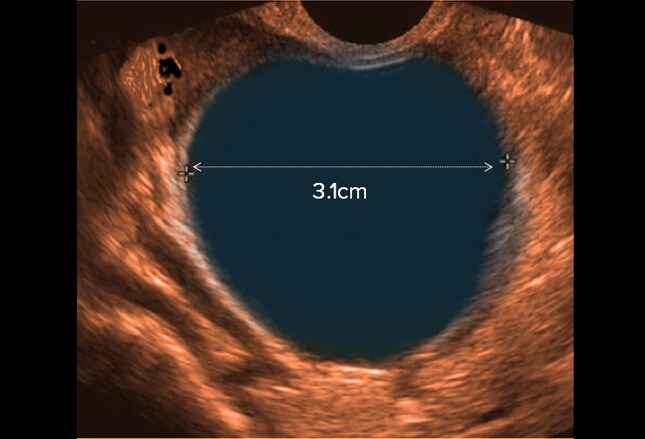

Ovarian Cancer What is ovarian cancer? Diagram of the ovaries showing different types of ovarian cancer Imaging tests are then carried out to look for cysts and tumours on the ovaries. This is usually done by transvaginal ... Retrieve Full Source

Ultrasound And Assessment of Ovarian Cancer Risk

Al cysts, tubal and inflammatory diseases, or endometriosis (Figs. 1 and 2). acteristics and classic types of ultrasound morphology are appreciated, UKCTOCS = United Kingdom Collaborative Trial of Ovarian Cancer Screening, ... Retrieve Content

WHAT ARE OVARIAN CYSTS? - Prgmea.com

WHAT ARE OVARIAN CYSTS? An ovarian cyst is a collection of fluid within the ovary. There are many different types of ovarian cysts. Because of the fear of ovarian cancer, cysts are a common cause of concern among women. But, it is important to know that the ... Read Here